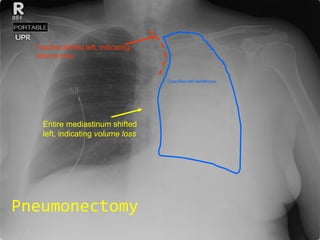

Pneumonectomy

Pneumonectomy Entire mediastinum shifted left, indicating  volume loss Opacified left hemithorax Trachea shifted left, indicating  volume   loss